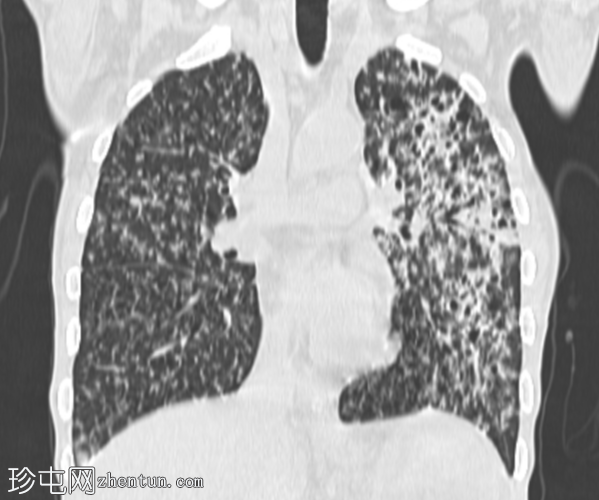

冠状肺窗

CT扫描图像:双侧肺部广泛粟粒性结节。

双侧肺部广泛粟粒性结节及树芽征,伴左上叶空洞及小气腔实变。